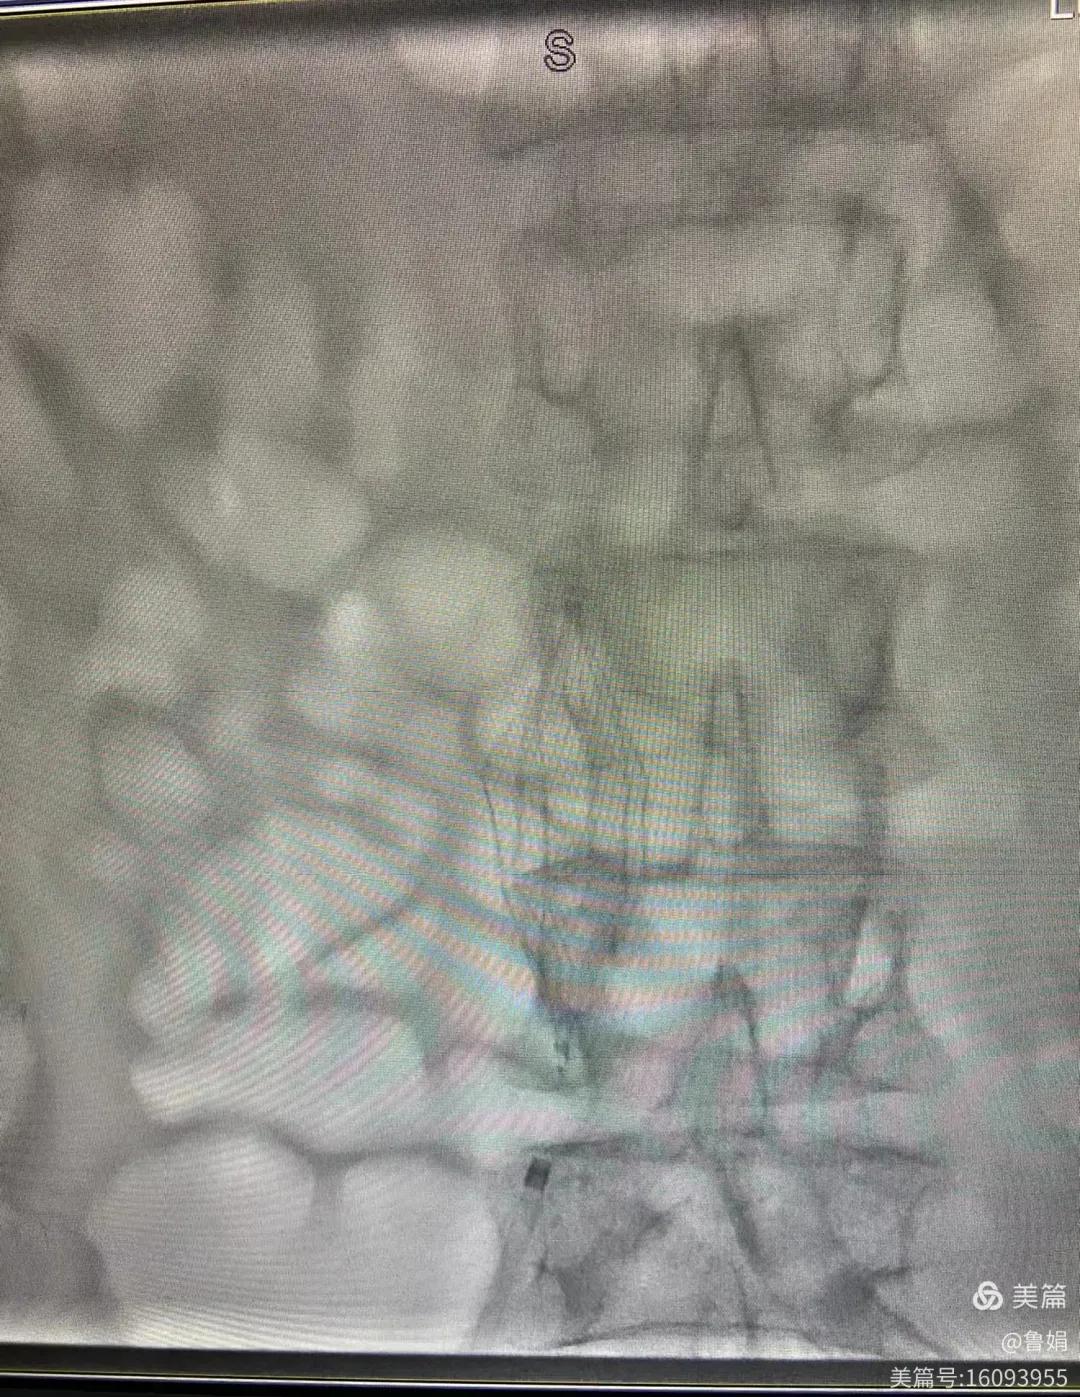

圖片術(shù)后濾器順利植入

11月3日,漯河市中醫(yī)院血管外科副主任周創(chuàng)業(yè)與腦二科介入醫(yī)生孫亞中,兩位醫(yī)生為一位腦梗死伴下肢深靜脈血栓形成患者成功開展下腔靜脈濾器置入術(shù)。

經(jīng)認(rèn)真查看患者病例,探討患者病情及術(shù)中潛在風(fēng)險(xiǎn)因素,多科會(huì)診后急診為患者開展介入手術(shù),術(shù)中周創(chuàng)業(yè)副主任、孫亞中副主任中醫(yī)師二人通力合作,手術(shù)順利,病人術(shù)中出血少,生命體征平穩(wěn),現(xiàn)在腦二科病房繼續(xù)對(duì)癥治療。(介入中心:魯娟)